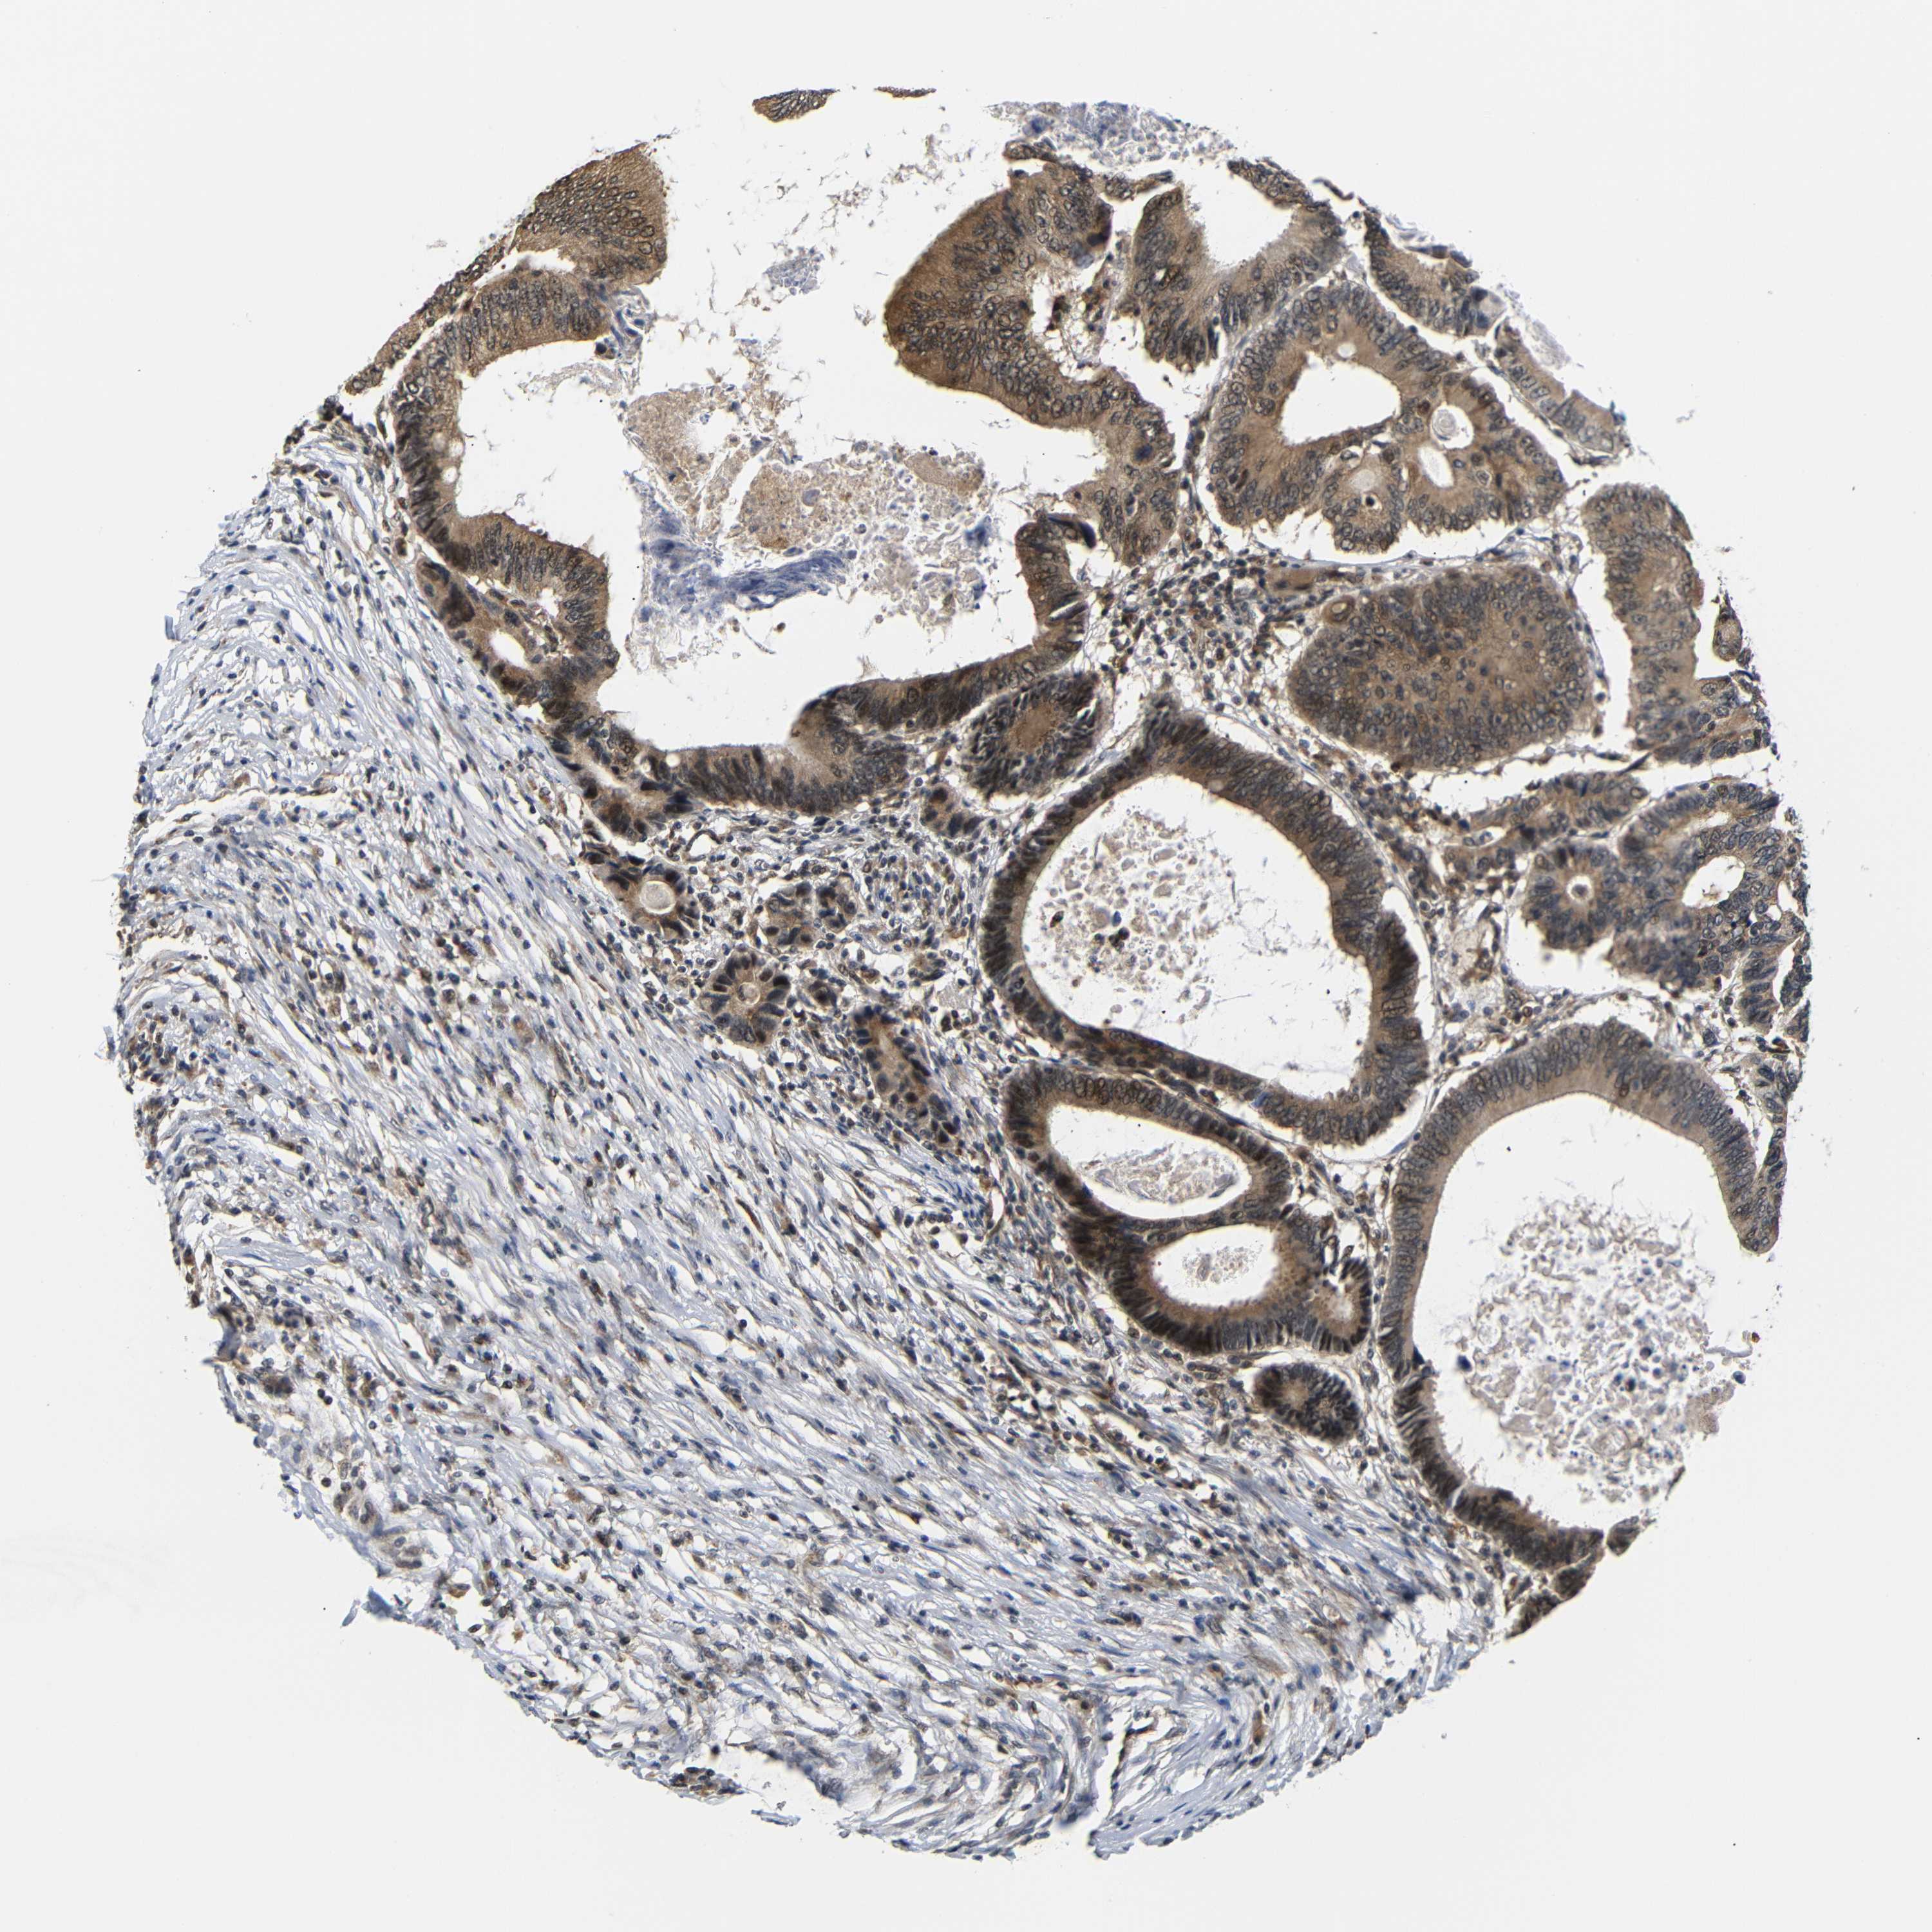

CANCER COLORECTAL CANCER Show tissue menu

Colorectal cancer

Human cancer

Colon adenocarcinoma